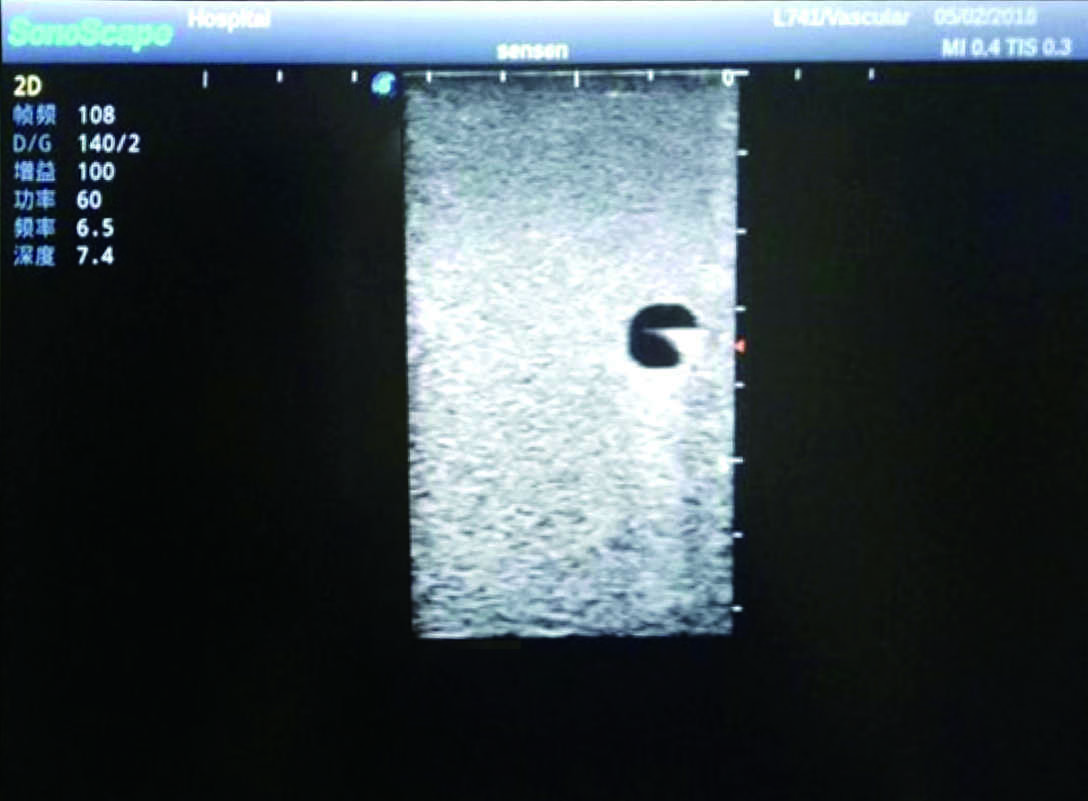

3)   Clear and real images of the tissues and organs (basilic vein and superior vena cava)

5)   Observe the guide wire marches